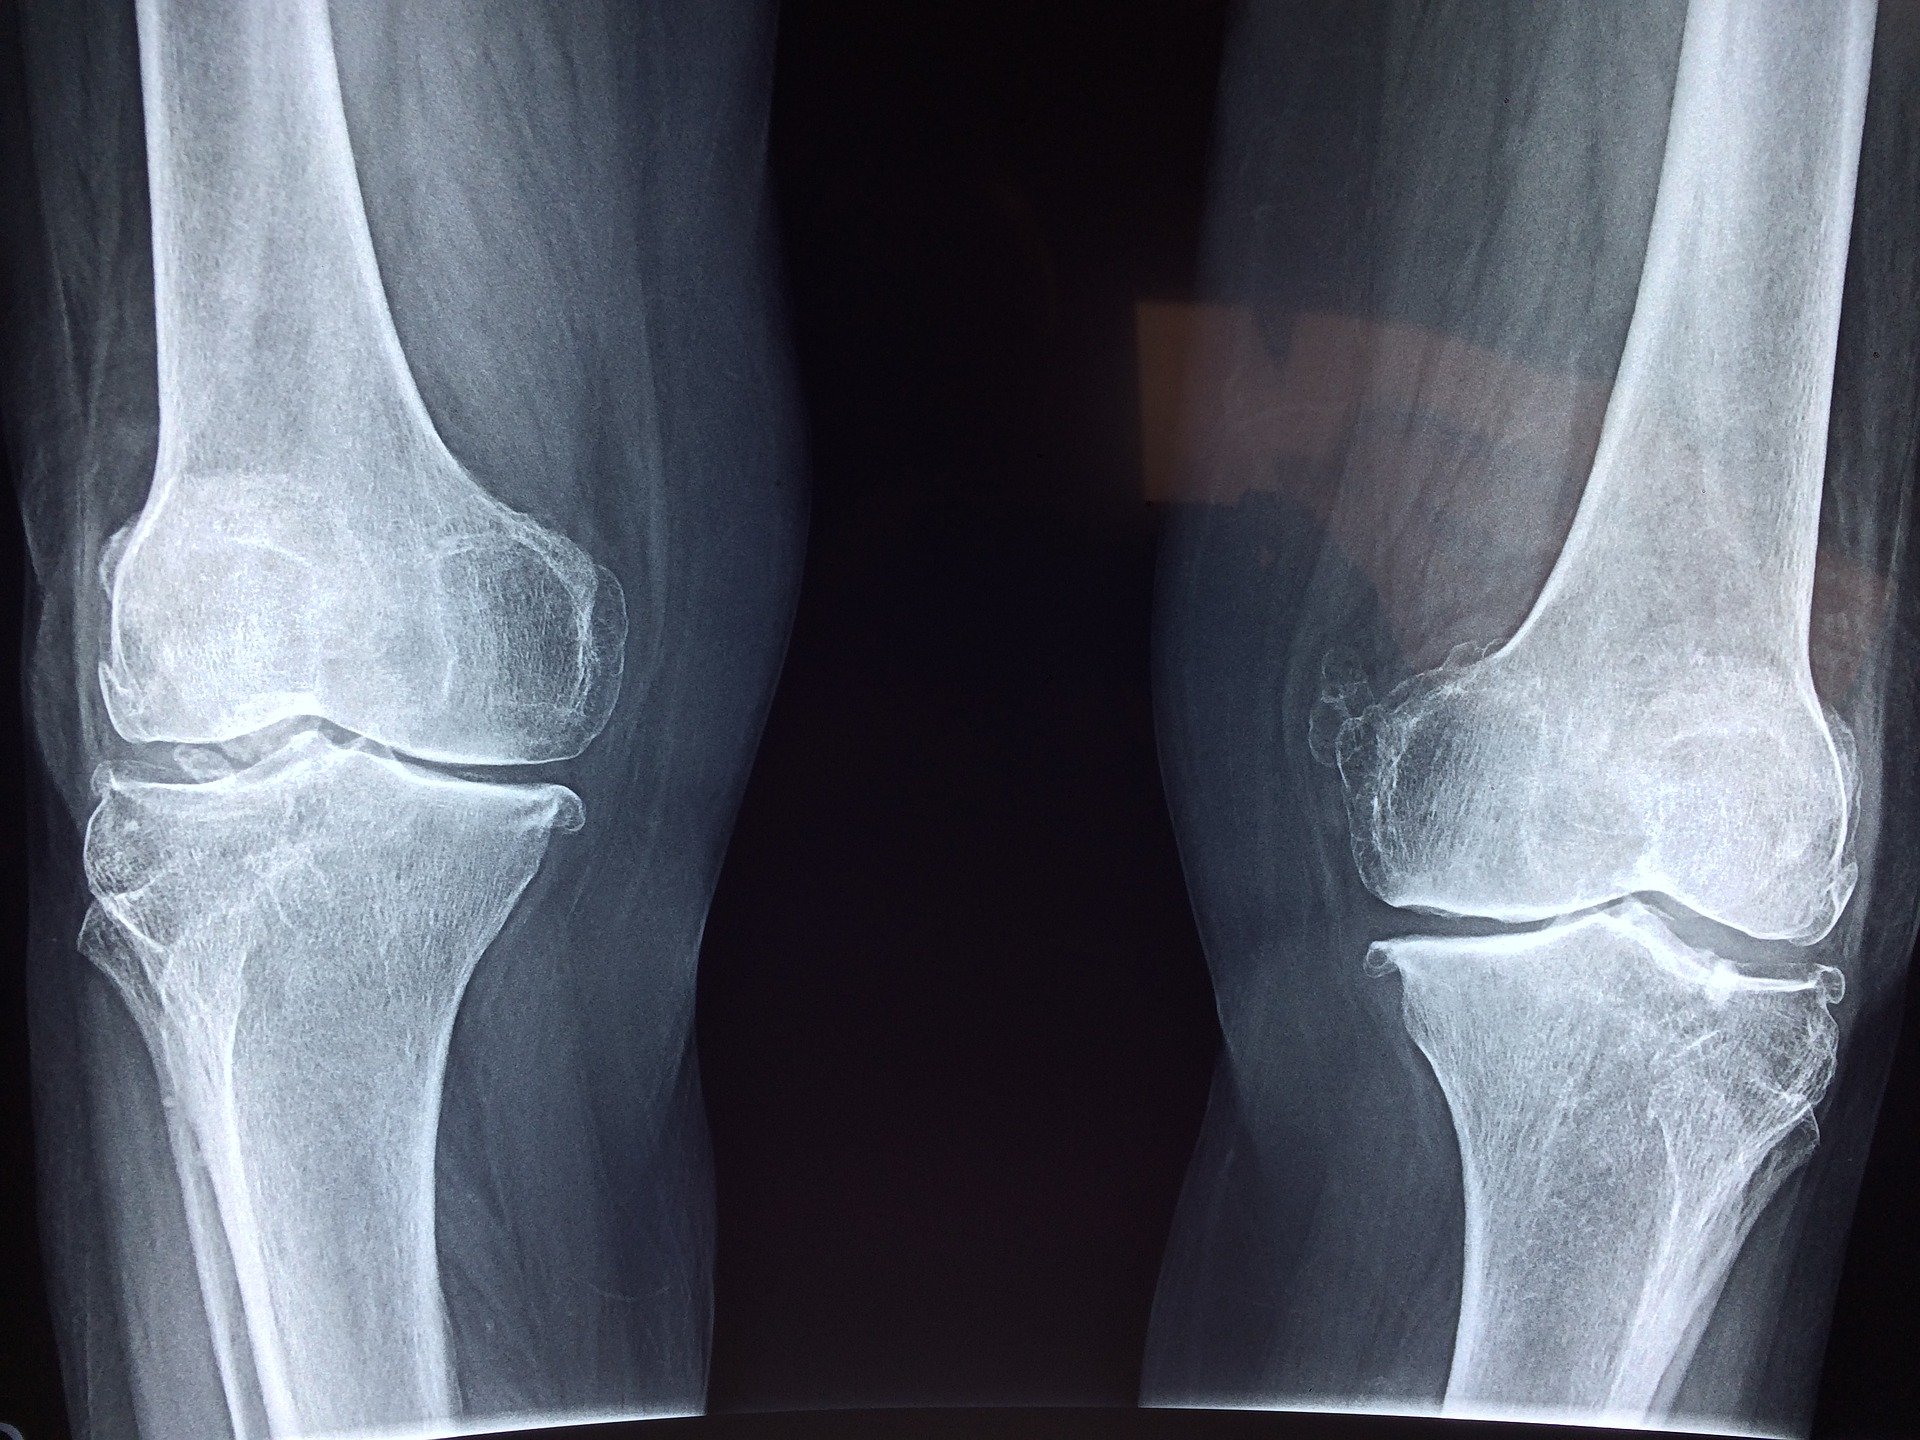

Opuchnięte kolano to sygnał, by udać się do lekarza, jeśli opuchlizna trwa dłużej niż kilka dni. Jednak istnieją domowe sposoby, które pomagają i przynoszą ulgę w tym trudnym czasie. Dzięki nim można uporać się z obrzękami i zebraną wodą w kolanie. Uśmierzają ból i łagodzą objawy.